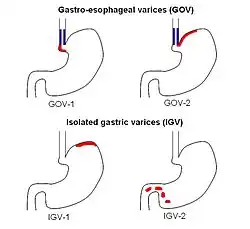

The Sarin classification of gastric varices identifies four different anatomical types of gastric varices, which differ in terms of treatment modalities:[1]

- Type 1 Gastroesophageal Varices: Esophagus extending to lesser curvature of stomach

- Type 2 Gastroesophageal Varices: Esophagus extending to greater curvature of stomach

- Type 1 Gastric Varices: Isolated to the fundus

- Type 2 Gastric Varices: Anywhere in the stomach, or duodenum

Type 1 isolated gastric varices were seen only in primary cases (i.e. without prior sclerotherapy) in the original study of Sarin et al. (1992), while type 1 gastroesophageal varices were the most common overall.[3]

Other classification systems include Hashizume's classification and Arakawa's classification.[1]